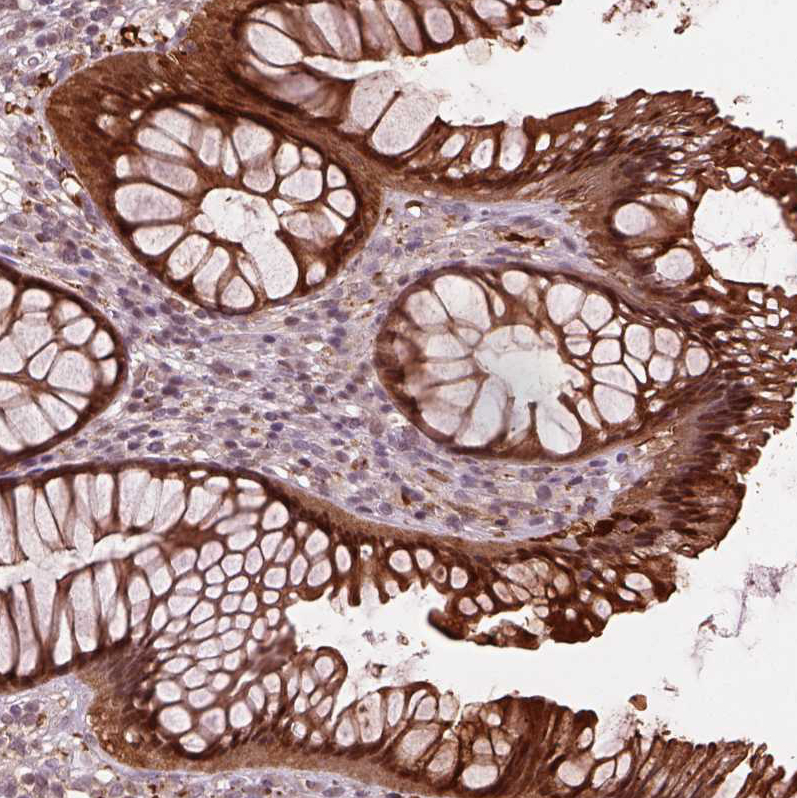

Immunohistochemistry analysis in human rectum and skeletal muscle tissues using HPA073666 antibody. Corresponding SRI RNA-seq data are presented for the same tissues.